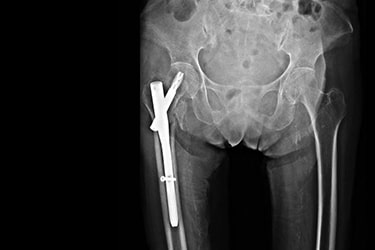

Fraturas subtrocantéricas

Localizam-se abaixo da região trocantérica. São bem menos frequentes que as fraturas anteriores, e costumam ocorrer em duas faixas etárias: dos 20 aos 40 anos, ou acima dos 60 anos. A cirurgia recomendada para este tipo de fratura é fixação com hastes intramedulares e parafusos. Contudo, existem situações que usam-se placas e parafusos.